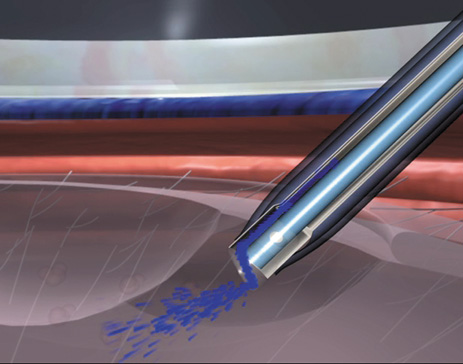

A mature cataract precludes visualization of the fundus. A B-scan ultrasonographic examination provides a real-time, two-dimensional (2D), cross-sectional image of the globe along the marked axis of the probe (Fig. 3). Cataracts are more common in patients with chronic retinal detachment, prior trauma, or intraocular tumors; therefore, a B-scan study is helpful in excluding structural posterior segment pathology before surgery on a mature cataract. Although a negative result to B-scan evaluation is reassuring, the surgeon should remember that it does not predict postoperative visual outcome. The B-scan can be thought of as a picture of Cincinnati from an airplane; the office buildings may all be standing, but you cannot tell whether the people in them are working.